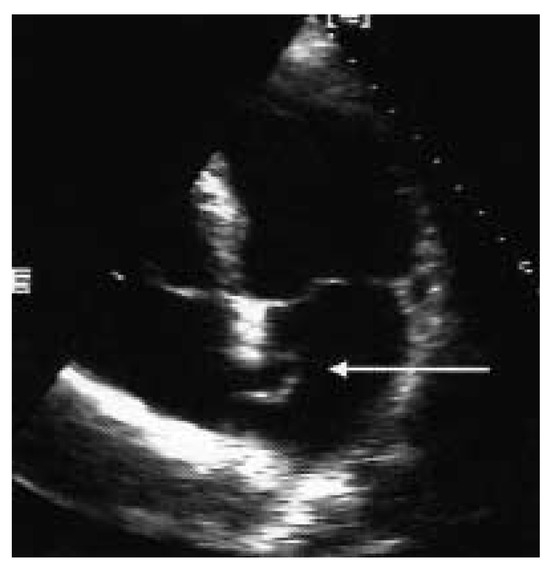

Nach eingehender Diskussion der Befunde mit allen involvierten Kollegen, der Patientin und ihren Angehörigen wurde die Patientin zum perkutanen Verschluss des ASD an die Kardiologie des UniversitätsSpitals Zürich überwiesen. In der invasiven Herzkatheteruntersuchung konnte eine koronare Herzkrankheit und eine pulmonal-arterielle Hypertonie ausgeschlossen werden. Der mittlere pulmonal-arterielle Druck betrug 19 mm Hg und der pulmonale Widerstand 81 dyn×sec×cm–5. Vor Verschluss des Vorhofseptumdefektes, welcher in Narkose und unter transösophagealer Überwachung durchgeführt wurde, konnte oxymetrisch kein Rechts-Links-Shunt nachgewiesen werden. Der Links-Rechts-Shunt betrug unter diesen Bedingungen zudem auch nur 14%. Nach Sondieren des Vorhofseptumdefektes wurde mittels Messballon eine ASD-Grösse von 19 mm gemessen. Es wurde ein Amplatzer-ASD-Occluder® 20 mm im Vorhofseptum plaziert. Aufgrund der Lokalisation des ASD mit praktisch fehlendem Saum gegen die Aorta kam der Schirm nahe der Aortenwurzel zu liegen (Figure 3 and Figure 4). Die orale Antikoagulation wurde in der Folge abgesetzt und als Nachbehandlung erhielt die Patientin 100 mg Aspirin® und 75 mg Plavix® für drei Monate, gefolgt von Aspirin® 100 mg für weitere drei Monate. Ebenfalls wurde für sechs Monate eine Endokarditisprophylaxe durchgeführt. Nach dem Eingriff war die Anstrengungsdyspnoe praktisch behoben und die transkutane Sauerstoffsättigung betrug nun im Stehen und unter Belastung immer über 90%. In der transthorakalen Echokardiographie sechs Monate nach dem Eingriff konnte kein Shunt auf Vorhofebene mehr nachgewiesen werden. Der Amplatzer-Occluder lag in regelrechter Position. Weiterhin war der systolische pulmonal-arterielle Druck nicht erhöht.

Figure 3.

TEE vor (A) und nach (B) Verschluss mit Amplatzer-Occluder 20 mm. Zu beachten die Position des ASD nahe der Aortenwurzel.